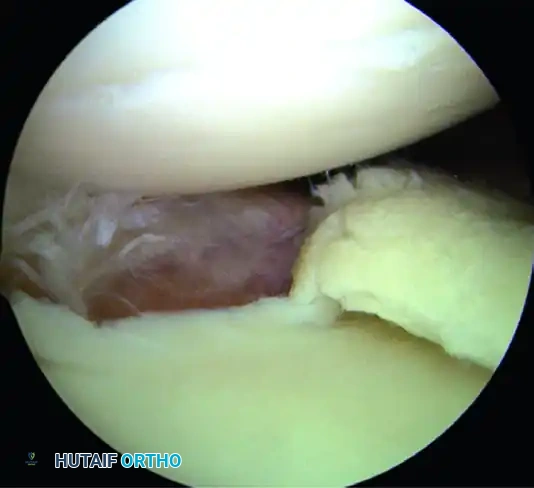

Identify the specific pathology. The spectrum of instability lesions includes soft tissue Bankart tears, bony Bankart lesions, Anterior Labroligamentous Periosteal Sleeve Avulsions (ALPSA), and Glenoid Labral Articular Disruptions (GLAD).

A, Soft tissue Bankart lesion.

B, Bony Bankart lesion.

C, Anterior labral periosteal sleeve avulsion (ALPSA).

D, Glenoid avulsion of glenohumeral ligament.

E, Glenoid labral articular disruption (GLAD).

F, Juvenile glenoid avulsion of the glenohumeral ligament.